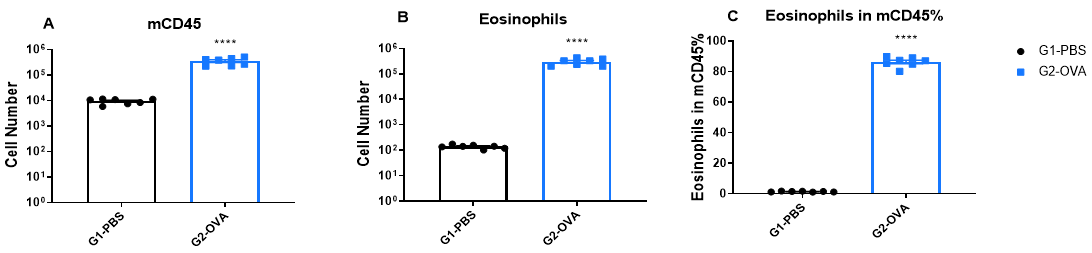

Immune Cell Infiltration in Bronchoalveolar Lavage Fluid (BALF) of Asthmatic Mice

Increased Immune Cell number in BALF of OVA-induced mice compared with controls. BALF was collected at the end of the experiment and CD45+ cells number (A), eosinophils number (B) and the percent of eosinophils in CD45+ cells (C) were measured by flow cytometry.

IgE Induction in Serum of Asthmatic Mice

Increased IgE levels in serum of OVA-induced mice compared with controls. Serum was isolated at the end of the experiment and concentrations of OVA-specific IgE (A) and serum total IgE (B) were measured using ELISA.